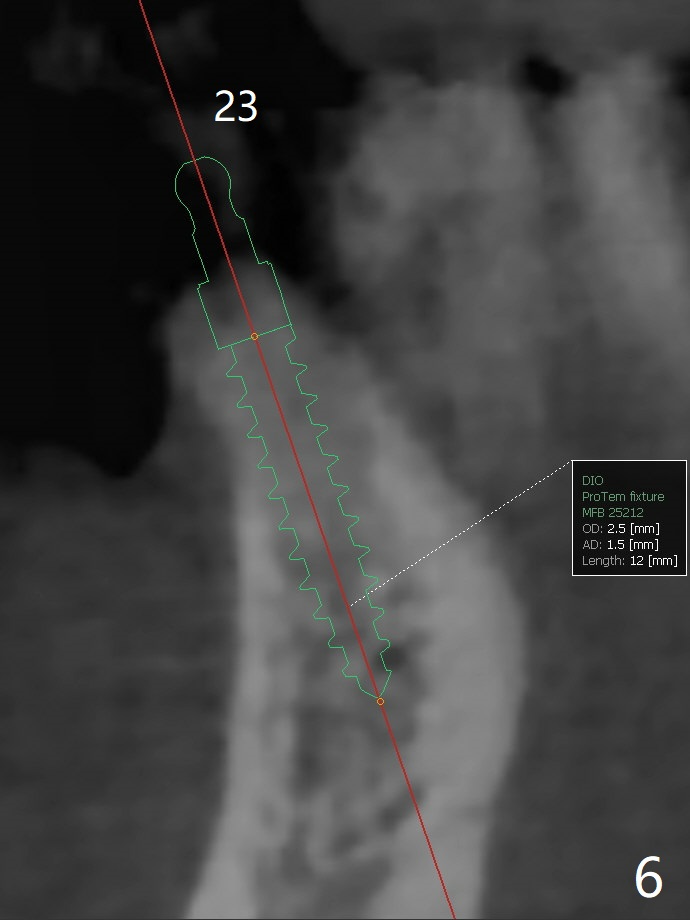

57岁女,口干症,前一个月(23,29号牙),三个月(26号牙)拔除植骨,可能需要再等一个月(出差)才能手术,会不会太早植牙?骨质还不够